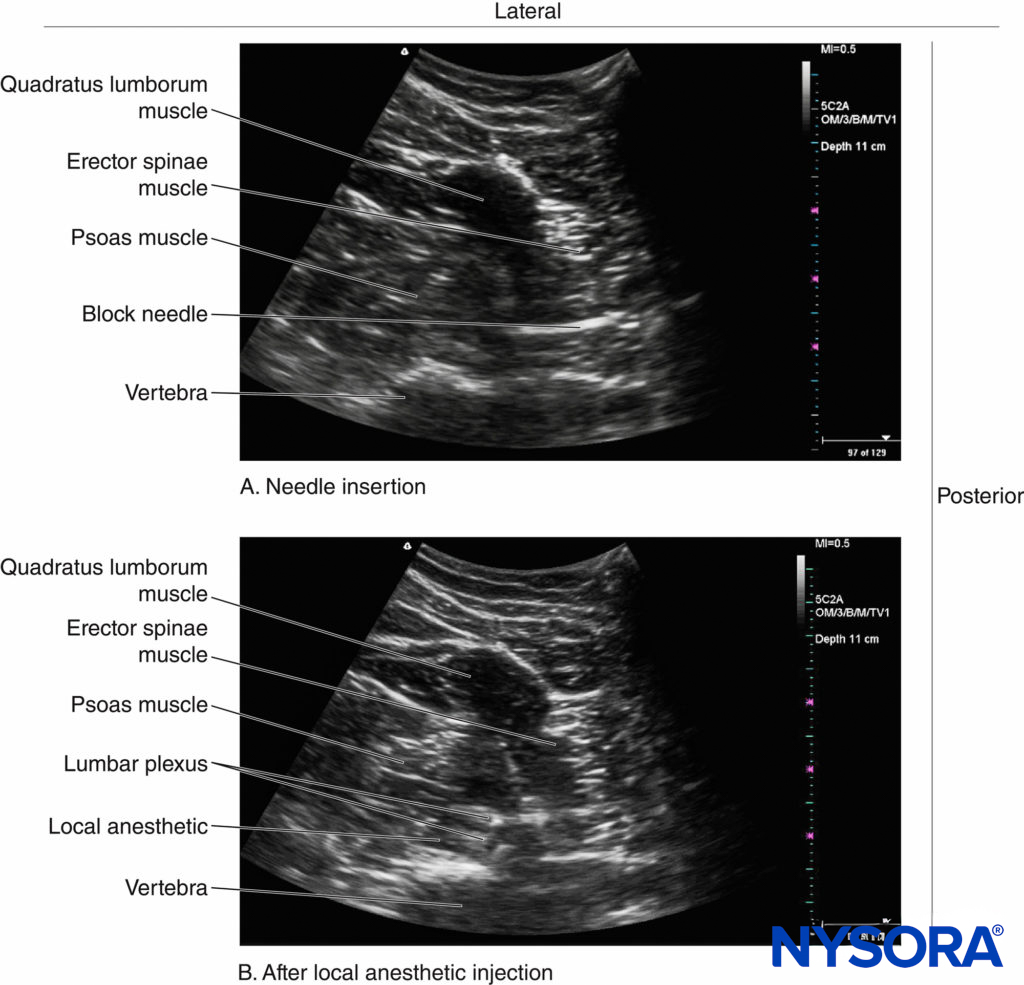

This view represents the transverse view of the anatomy relevant for LPB through the L4–5 intertransverse space. A line is then drawn on the patient’s back extending from the center of the medial end of the IS transducer to the midline (back). A nerve block needle is inserted 4 cm from the midline along this line (Figure 28) and gradually advanced anteriorly under real-time US guidance (in-plane needle insertion; Figure 29a) until the needle tip is close to the L3 nerve root. Nerve stimulation should be used in conjunction with US to confirm correct needle placement, after which 20–30 mL of ropivacaine or levobupivacaine 0.5% is injected slowly while visualizing the perineural spread of the drug in the posterior aspect of the psoas muscle (Figure 29b).

FIGURE 29. Transverse sonograms showing (A) the direction of needle insertion relative to the lumbar paravertebral anatomy and (B) the local anesthetic (LA) spread during a USG LPB using the shamrock method.

The technical challenge with this approach is that although the block needle is inserted in plane, visualizing the needle initially can be very challenging, since the sites for the US scan and needle insertion are separated by a considerable distance (see Figure 28). Nevertheless, with experience, needle visualization can be easily accomplished.